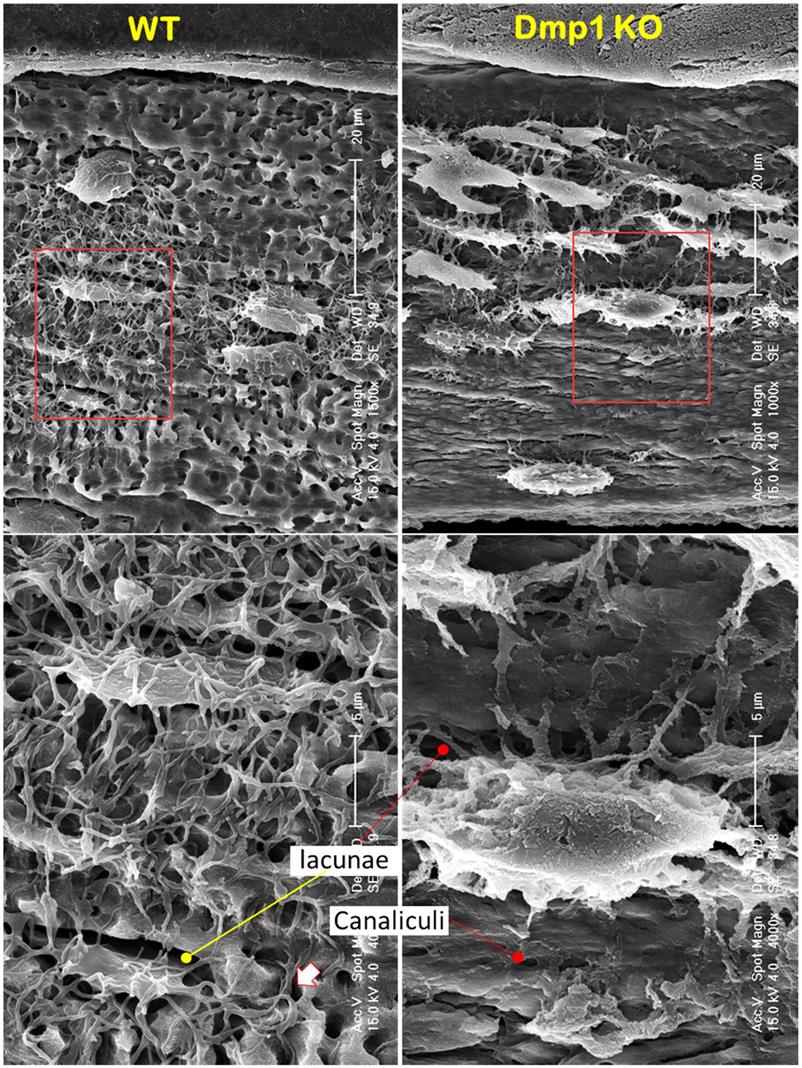

A Drastic Increase in Osteoblast-Like Cells in Dmp1 Null Mice (A Hypophosphatemia Rickets Model)

A loss of the “wire mesh” structure and a change of Ocy morphologies in the Dmp1 null mandible (Representative data from 4 animals). Acid-etched SEM images from a 7-week-old mandible bone revealed a “rod and wire mesh-like” structure in the control sample, which maintained an intact bone structure (left, n = 4). In contrast, the age-matched Dmp1 KO bone displayed a poorly formed mandibular bone, in which the “rod and wire mesh-like” structure was largely disappeared with striking changes in Ocy morphologies, including more cell numbers, an overall increase in cell size, a switch from spindle to olive shape, an increase in dendrite diameter, and a decrease in dendrite length.

Int J Biol Sci Image